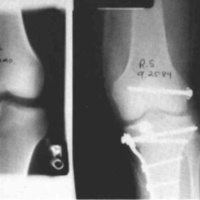

A twenty-nine year old male sustained a high caliber gunshot wound to the left knee (Fig. 4), traversing the lateral femoral condyle through the joint space and through the lateral tibial plateau. Open reduction internal fixation (ORIF) and ligamentous repairs were made. Postoperatively, the patient was placed in a standard cast brace due to the inability to provide adequate medial-lateral stability of the knee surgically (Fig. 5). The cast brace was attached to a continuous passive motion dynamic suspension system to restore and maintain motion (Fig. 6). At the time of the initial cast bracing, the patient had considerable soft tissue edema about the knee. The use of passive motion quickly reduced that swelling to the point where the cast brace provided little support. After one week, the cast brace was reapplied with the addition of a varus producing strap (Fig. 7) and the patient began ambulation training and was discharged. (If atrophy or swelling should continue, the varus producing strap can be easily adjusted to maintain force on the knee and another cast change would not be required).

Figure 7:

Figure 8: